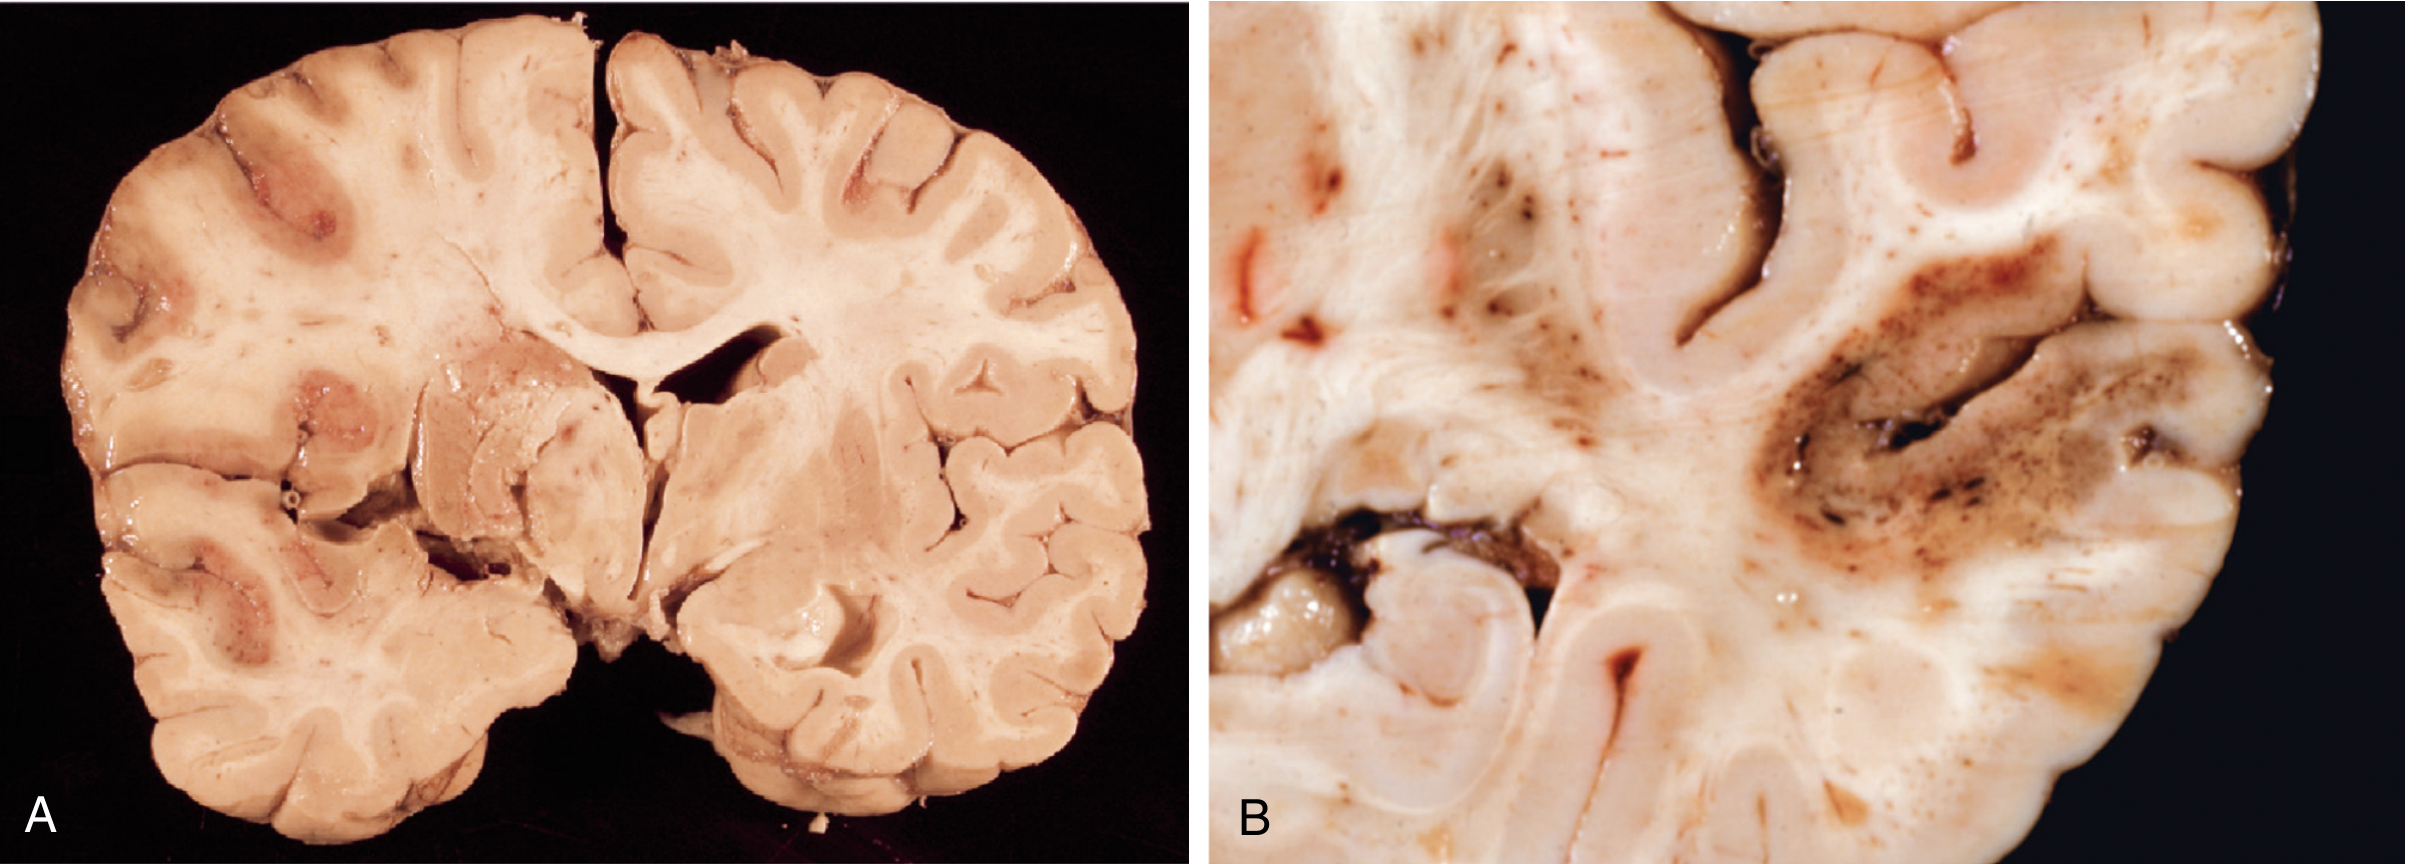

Fig 28.9 — A: Pale ischemic infarct (MCA territory, left hemisphere). B: Hemorrhagic infarct with punctate hemorrhages from ischemia-reperfusion injury (temporal lobe)

(A) — Pale/anemic infarct: MCA territory, no blood re-entry, tissue appears pale and soft. (B) — Hemorrhagic infarct: punctate (petechial) hemorrhages from reperfusion injury — the classic appearance after embolic stroke with embolus lysis.